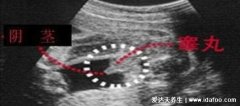

2、孕囊

生男生女其实看孕囊很准:看6-7周的孕囊数据,比如40*38*19,前面两长边的数据相近,还是第三条边长的两倍,这种孕囊形状偏长条,是标准的男宝宝。如果是40*33*27,这种三条边长度差不多的,孕囊形状偏圆形,那么是女孩的概率比较大。

注意:如果只有两个数据,比如40*26,是孕囊横截面的数据,不能用来看男女。